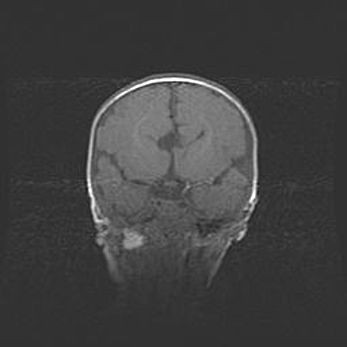

Мальформация Денди-Уокера. Киста задней черепной ямки.

Агенезия мозолистого тела.

Возраст: 2,5 месяца

Вес: 2420 г

Пол: женский

Окружность головы: 37 см

Срок гестации: 32 недели

Мальформация Денди—Уокера — редкий вид патологии ЦНС, представляющий собой врожденный порок развития каудального отдела ствола и червя мозжечка, ведущий к неполному раскрытию срединной (Мажанди) и латеральных (Лушка) апертур IV желудочка мозга. Для этогно синдрома характерна триада симптомов: гипотрофия червя мозжечка и/или полушарий мозжечка, кисты задней черепной ямки, гидроцефалия различной степени. В 70% случаев порок сочетается и с другими аномалиями головного мозга, в частности с агенезией мозолистого тела.